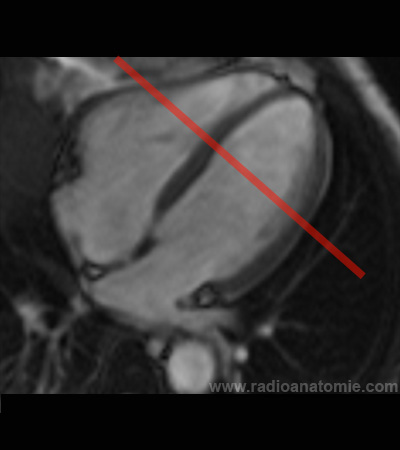

Radioanatomie et plans de coupe en IRM cardiaque

Plan 2 cavités

Plan petit axe

Plan chambre de chasse du ventricule gauche (LVOT)